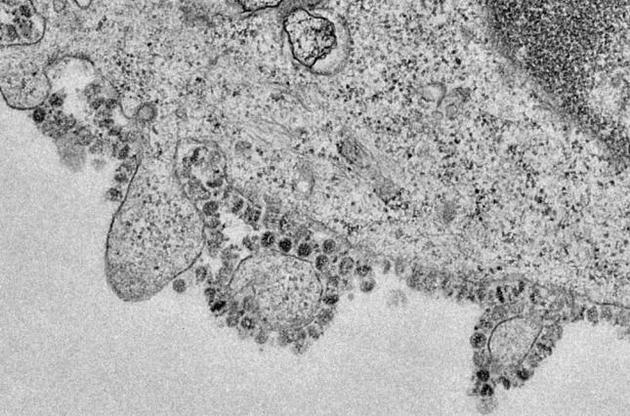

Вчені розшифрували геном вірусу ще місяць тому. Моделювання, яке провели дослідники, показало, що глікопротеїн (S-білок) на поверхні 2019-nCoV схожий на аналогічний білок спорідненого SARS. За допомогою цієї молекули SARS зв'язується з рецепторами ангіозинперетворючого ферменту 2 (Angiotensin-Converting Enzyme 2, ACE2), який бере участь у регуляції кровообігу. Цей зв'язок і є "воротами" для проникнення вірусу в клітину.

Тепер же вчені підтвердили цю гіпотезу в ході лабораторних досліджень. За допомогою зразків, які були зібрані в одного з пацієнтів в грудні, вчені заразили клітинні культури. Виявилося, що вірус може проникати тільки в ті клітини, на поверхні яких є рецептори АСЕ2.

Крім того, вірус інфікував навіть модифіковані клітини людей з АСЕ2-рецепторами кажанів, цивет і свиней - тварин, від яких людям вже передавалися коронавіруси. Вчені вважають, що нинішня епідемія стартувала саме з кажанів.